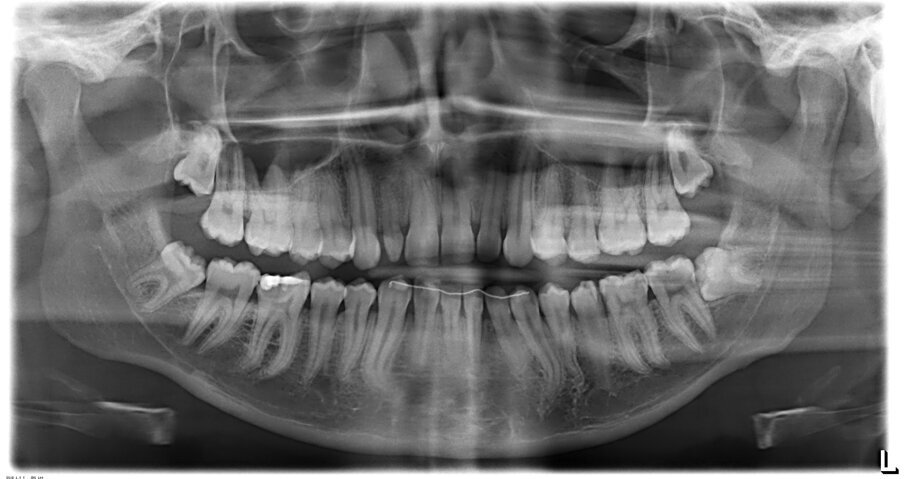

Fig. 1_Ortopanoramica iniziale.